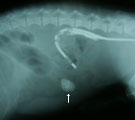

腹部レントゲン。結腸造影も同時施行。小腸領域にX線不透過性異物あり 術中所見。異物により腸閉塞をおこしていた。異物より前の小腸部分は充血 閉塞部分を腸切開し異物を取り出した。小石のようだった。 異物は庭の敷石のような小石で直径2cm位のものだった。

経過:受診時、全身状態はかなり悪化し腹鳴がみられた。CBCおよび血液生化学検査では低張性脱水を示した。腹部レントゲンにて小腸領域に直径2cmほどの角の丸いX線不透過性異物がみられた。この異物は1日経過しても移動がみられないことから小腸内異物による腸閉塞と診断した。ただちに開腹手術となった。小腸を探索し固い異物が腸内に嵌入した閉塞部分を見つけた。閉塞前の小腸部分は充血著明で、小腸粘膜傷害が推測された。閉塞部を切開し異物を取り出した。直径2cm位の庭に敷石のような小石だった。手術翌日より食欲の改善がみられ元気になった。